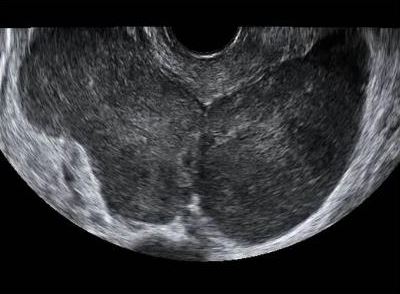

The ovary is a common site of metastases from malignant tumors. Most metastases in the ovaries originate in the gastrointestinal tract or the breast. The distinction between primary and metastatic ovarian neoplasm is of critical importance, since surgical cytoreduction is the treatment of choice for the former.